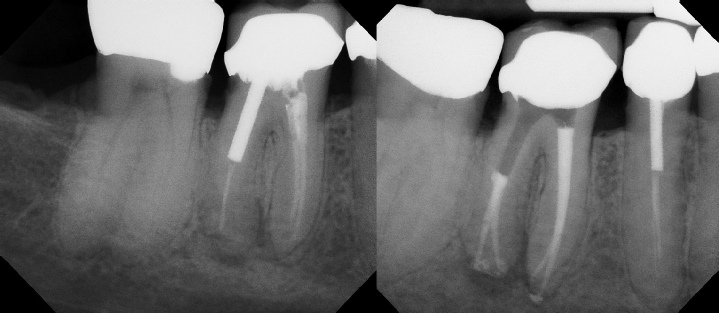

Root Canal Retreatment - Meriden 8 mos. recall Post-op Pre-op